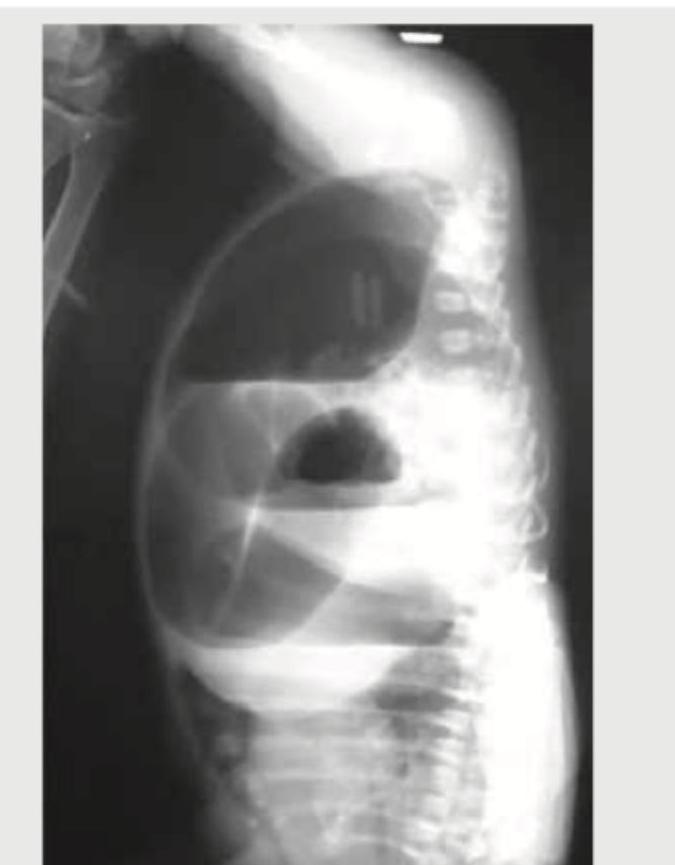

Explanation: ***Invertogram*** - An invertogram is a **lateral radiograph** of the abdomen with the patient **held upside down** to visualize the distal bowel gas pattern and evaluate for imperforate anus. - The image shows dilated bowel loops with gas, and the child's position (evident from the spinal curvature) is consistent with an inverted view. *Infantogram* - This term is **not a standard medical diagnostic procedure** or specific type of radiograph. - While it refers to an X-ray of an infant, it does not describe the specific technique or purpose shown. *Gynogram* - A gynogram is an older term for a radiological procedure involving the **injection of contrast material** to visualize female pelvic organs, particularly the uterus and fallopian tubes. - It is unrelated to the gastrointestinal tract or the patient's position in this image. *Vasogram* - A vasogram, also known as **vasography**, is a procedure that involves injecting contrast into the **vas deferens** or other vascular structures to visualize them. - This technique is used to assess male reproductive structures or blood vessels and is not applicable to evaluating bowel obstruction in an infant as depicted.